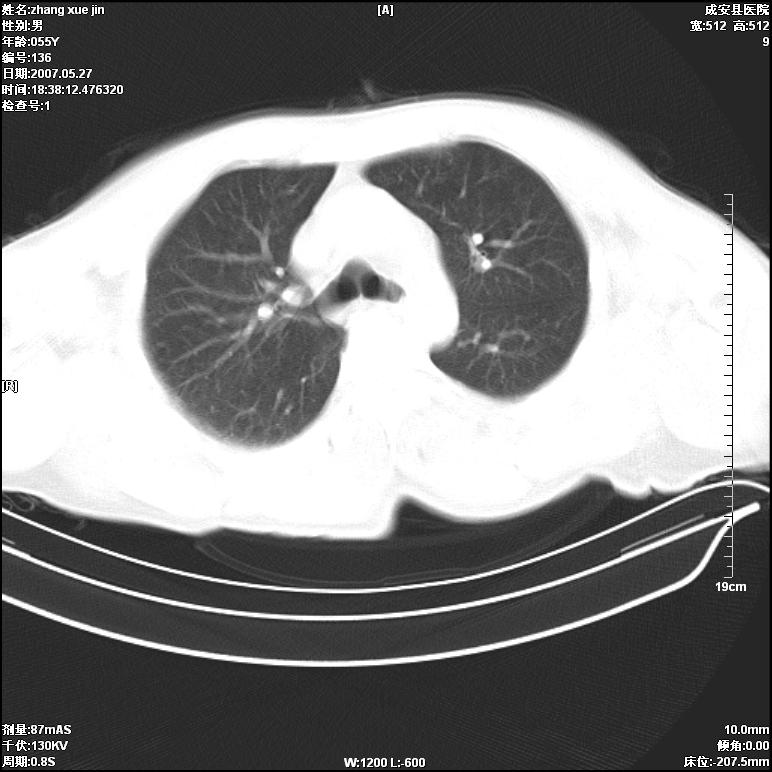

病人 男 53岁 从高处摔伤 行胸部ct检查,纵隔窗没事未上传,肺窗示,右侧胸膜下见条状稍高密度影,是胸膜下线还是右下肺轻度挫伤?意见不一,请分析。

右肺下叶胸膜下弧形窄带状模糊影,结合病史,考虑肺挫伤。

建议一周后复查,肺挫伤一般3~10天完全吸收。

应该把位置摆正,用吸气相或呼气相分别扫描,如果在深吸气相上无此影,支持正常肺坠积差。如果有那就是肺挫伤。

体位不正,左侧纵隔旁胸膜下亦见条带状略高密度影,考虑为坠积效应所致。